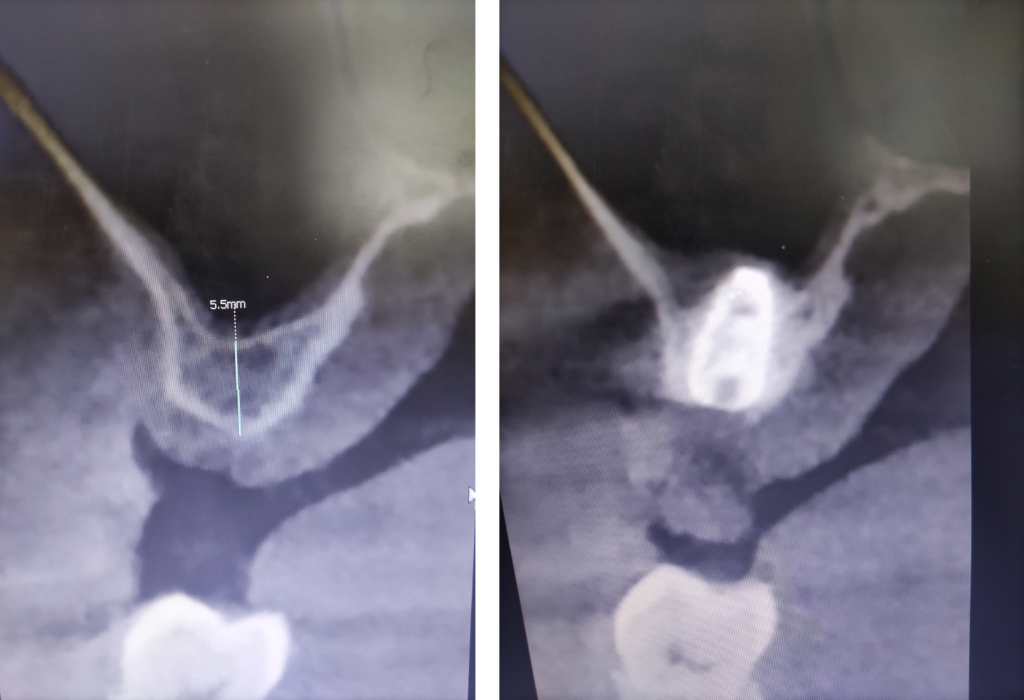

Расстояние до верхнечелюстной пазухи составило менее 6 мм.